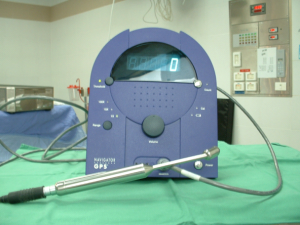

החומר הרדיואקטיבי מוזרק כארבע שעות עד 24 שעות לפני ניתוח. לאחר הזרקתו בעזרת מיפוי אפשר להדגים את מקום הבלוטה ולסמן את מיקומה על העור. ניתן להדגים גם בלוטות הקולטות חומר בשרשרת האינטרנל ממרי. בחדר ניתוח ניתן לאתר את הבלוטה בעזרת מונה גייגר על העור ובשדה הניתוח (תמונה 52.12).

|

|